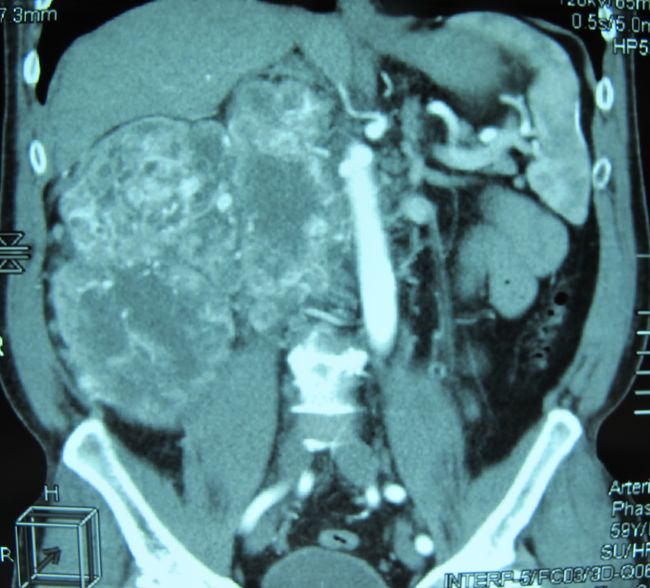

Опухоль правой почки, сдавливающая нижнюю полую вену

Опухоль правой почки (компьютерная томография)